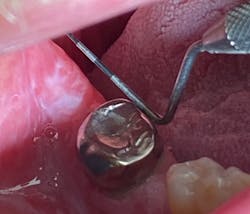

As I suspected, the initial diagnosis for this patient was lichen planus (LP) with ulcerative tendencies, even though there were no real prominent ulcers presenting at the time. The burning in the mouth that the patient was experiencing was more or less what initiated suspicion of the diagnosis.

Here’s a quick refresher on lichen planus. LP is an inflammatory condition that affects the mucus membranes of the mouth. Symptoms of burning, itching, pain, and overall discomfort can range from mild to severe. LP is a T-cell autoimmune disease commonly found in the fourth decade of life, and it affects men more than women.1 The buccal mucosa, tongue, and gingiva are the most common oral areas affected.1